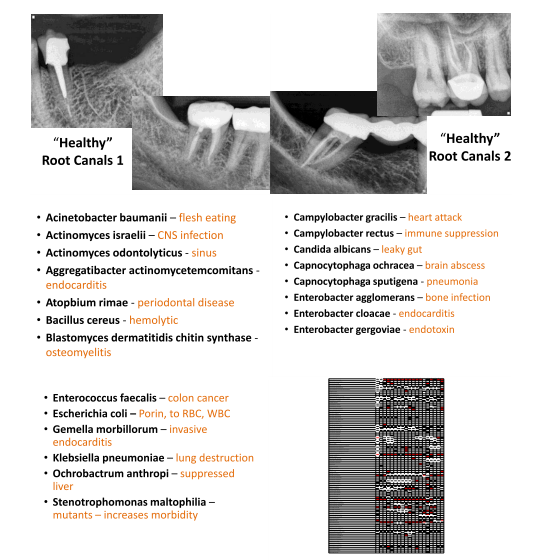

I dream that dentistry will finally discover

hundreds of microbes living under cover

Heart disease and even cancer

are not a normal healthy answer

Root canals have no MHC

so they become your enemy

I dream we’ll use our DNA

to chase the anaerobes away

When immune cells are killing bugs

the “healthy” microbes are living snug

That bone dissolves during immune protection

and “healthy” looking roots are full of infection

And those pathological microbes fill our bodies

every organ providing lobbies

The “healthy” root canals are doing us dirt

those are the ones that really hurt